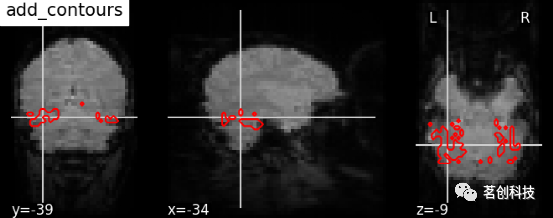

display.add_contours(img, levels=[.5], colors=' r '):添加轮廓线。

display = plotting.plot_anat(mean_haxby_img, title="add_contours",

cut_coords=[-34, -39, -9])

display.add_contours(haxby_mask_filename, levels=[0.5], colors='r')